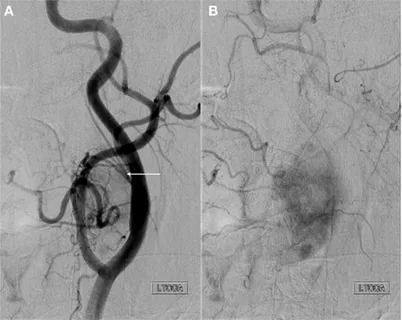

Moyamoya disease is a rare, progressive cerebrovascular condition in which the major arteries at the base of the brain (the internal carotid arteries and their branches) gradually narrow and eventually occlude. In response, the brain develops a network of tiny collateral blood vessels to try to compensate for the reduced blood flow. These fragile collateral vessels create the characteristic “puff of smoke” appearance on angiography that gives the disease its Japanese name (moyamoya).

While these collateral vessels represent the brain’s attempt to maintain blood flow, they are inadequate substitutes for the large arteries they replace. Patients with Moyamoya disease are at significant risk for ischemic stroke (from insufficient blood flow), hemorrhagic stroke (from rupture of the fragile collateral vessels), and progressive cognitive decline.